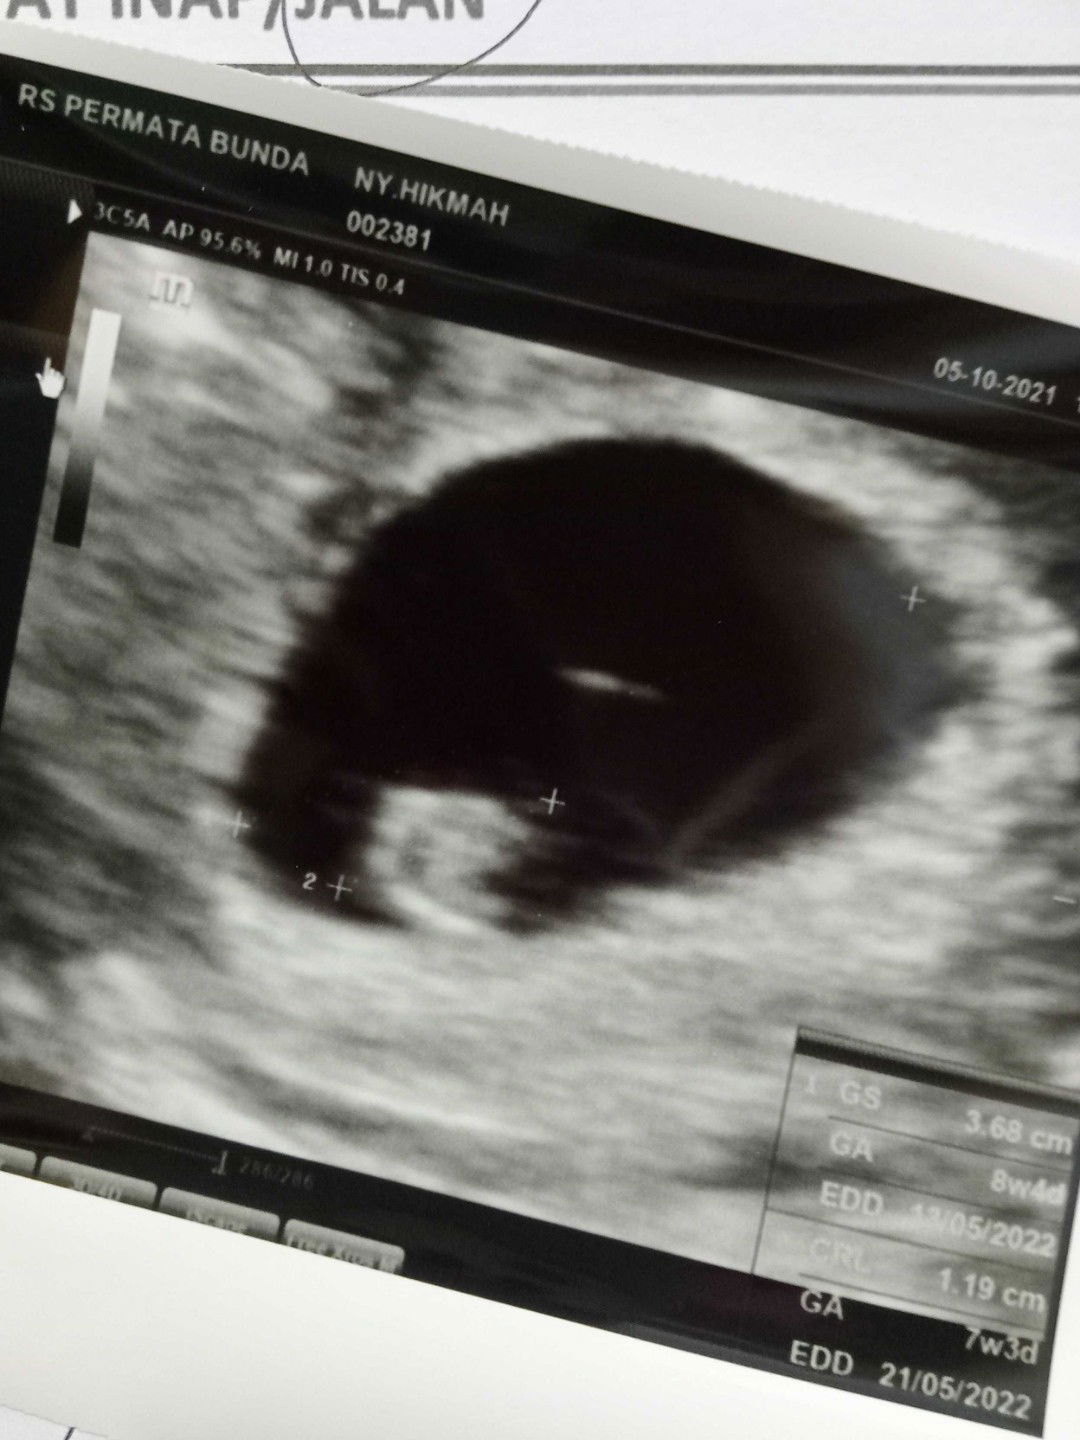

Jagoan kecil ku